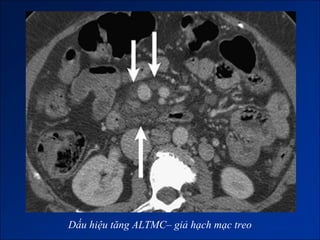

Dấu hiệu tăng ALTMC

Dấu hiệu tăng ALTMC– giả hạch mạc treo